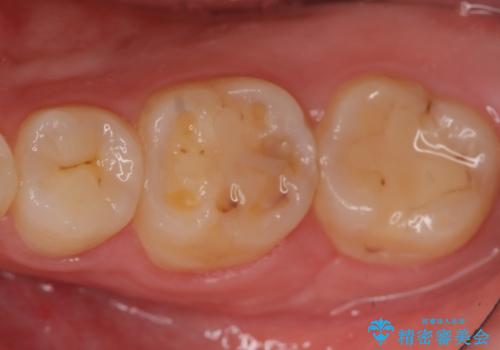

セラミックインレー 虫歯治療